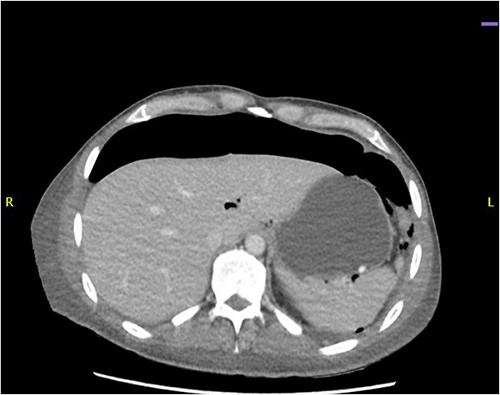

CT abdomen revealed a large amount of free air throughout the abdomen, mostly localized anterior, but also perihepatic, perigastric, paracolic, and perisplenic (Figs 1 and 2).

CT abdomen showing a large amount of free air mostly localized anterior.